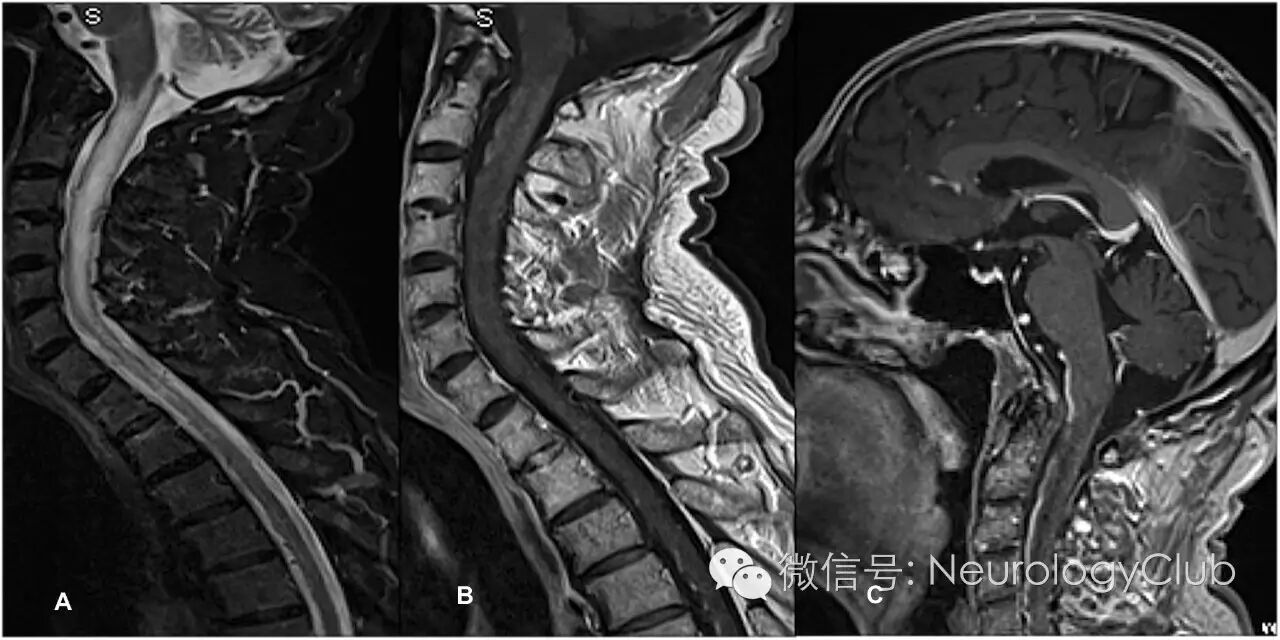

75岁男性,主诉进行性加重的步态障碍和四肢痛性感觉异常1年。既往史包括高血压和中度血友病甲。查体提示痉挛性四肢轻瘫伴括约肌功能障碍,下肢行走数米即感到无力。无感觉平面。颅神经检查阴性。结合6月前的影像学,临床诊断为颈髓病,但确切病因尚不知晓。脊髓MRI提示广泛弥漫的颈髓肿胀(图1)。头颅MRI正常。行影像学检查前患者未服用任何糖皮质激素。

(图1:A:矢状位T2WI;B:矢状位T1WI;C:矢状位T1增强)

MRI提示弥漫颈髓肿胀以及脊髓前静脉扩张。这些改变提示颅内硬脑膜动静脉瘘(DAVF)伴髓周静脉引流,后经脑血管造影证实。该瘘的供血来自脑膜中动脉和左侧小脑上动脉(图2)。尝试Onyx栓塞脑膜中动脉不幸失败。改用Histoacryl经动脉栓塞左侧小脑动脉获得成功。1年后,患者可脱离工具轻松行走。MRI和脑血管造影可见脊髓水肿和DAVF消失(图3)。